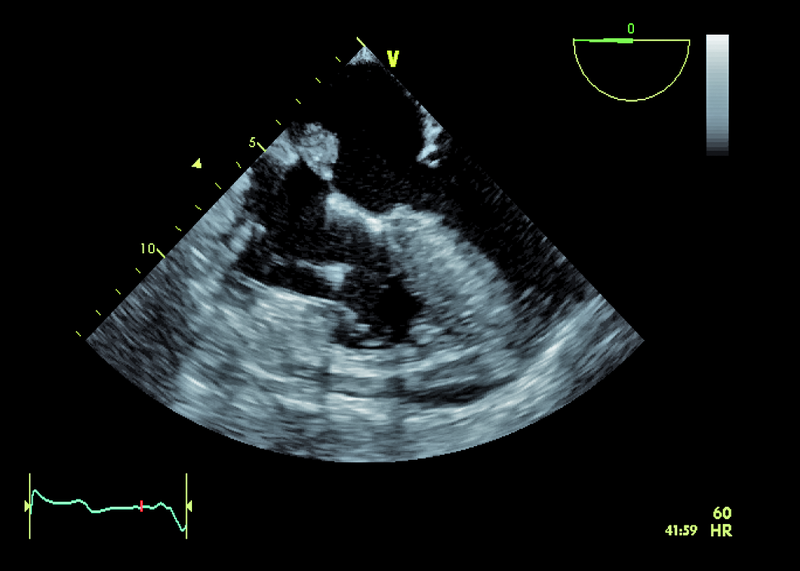

Kobieta, lat 55. Jakie patologie można rozpoznać na zamieszczonych rycinach?

1. Guz przegrody międzyprzedsionkowej (ryc. 1-3).

2. Mały ubytek przegrody międzyprzedsionkowej z przeciekiem lewo-prawym (ryc. 1-3).

4. Istotny przerost przegrody międzykomorowej (ryc. 1, 2, 5).